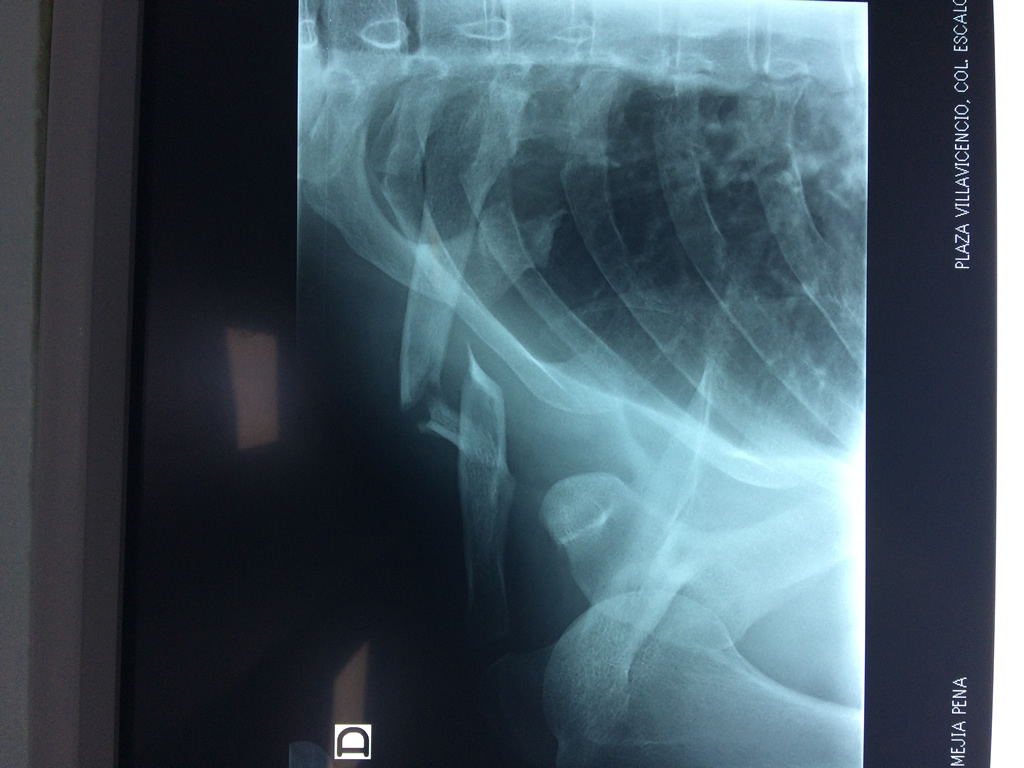

Cirugías de Hombros - Clavícula

La clavícula es un hueso largo, con forma de "S" itálica, situado en la parte anterosuperior del tórax. Junto con la escápula forman la cintura escapular. Se puede palpar por toda su longitud y se extiende del esternón al acromion de la escápula, siguiendo una dirección oblicua lateral y posterior.